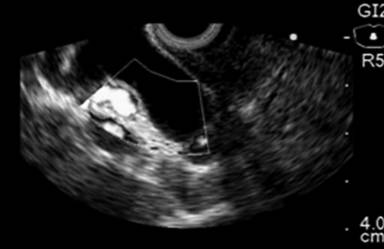

The common bile duct was visualized using a linear echoendoscope (GFUCT160, Olympus, Tokyo, Japan). Color Doppler US was used to identify the vascular anatomy. The dilated bile duct was punctured with a 19 gauge FNA needle (EUSN-19-T, Cook Endoscopy, Winston-Salem, NC, USA). The puncture position was chosen based on EUS evaluation, at the common bile duct above the tumor, through the distal part of the duodenal bulb (Figures 1 and 2).

Figure 1. EUS linear image demonstrating common bile duct dilatation. |